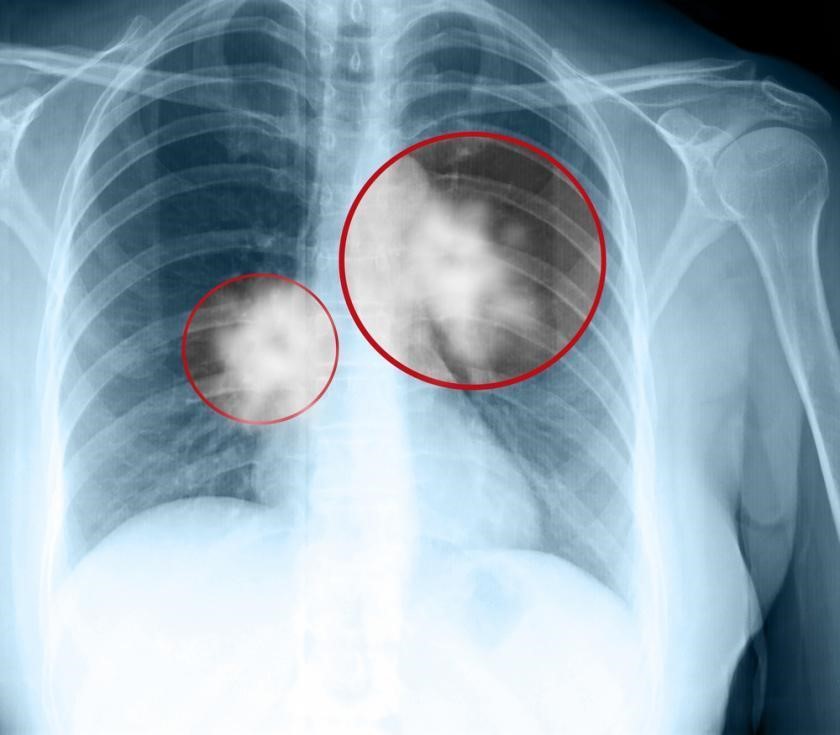

虽然许多人可能会将疫苗混淆为一种可以预防疾病的药物,但实际上该疫苗有助于激活身体的免疫反应。 非小细胞肺癌疫苗Cimavax通过刺激患者的身体释放针对表皮生长因子(发出肿瘤生长信号)的抗体。在肺癌患者中,这可以防止肺肿瘤的生长和扩散,并可以将晚期肺癌转化为更易于治疗的慢性病。

然而,Roswell Park并不打算将其Cimavax研究限于肺癌治疗。该研究所希望将疫苗提升到一个新的水平,探索其潜力,以此彻底防止肺癌的复发甚至初始发作。目前,这种药物有助于延长古巴肺癌患者的生命。研究所招募90位既往接受过治疗的晚期非小细胞肺癌患者,使用最佳剂量和最低副作用的非小细胞肺癌疫苗联合PD-1检查点抑制剂(opdivo)进行治疗,观察它们是如何对III-IV期非小细胞肺癌患者起作用的。

去年九月,她被告知仅剩两三个月的生存期。 Lucrecia的腿部开始疼痛,被诊断为已经骨转移的四期肺癌。

放疗后,Lucrecia开始进行非小细胞肺癌疫苗注射“现在,她的肺部肿瘤已经消失了,肝脏上的病变也不见了,现在很顺利的处于非小细胞肺癌疫苗维持治疗阶段。